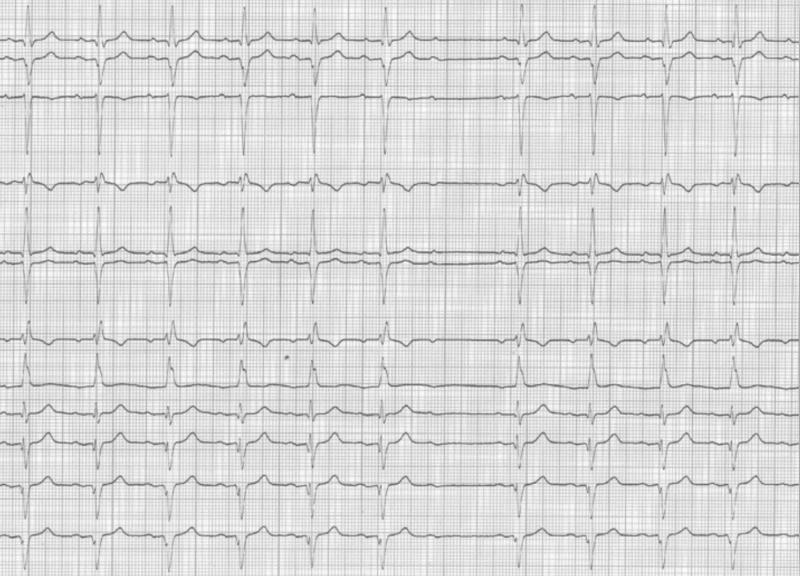

Fig 21 : Dissociation AV complète. C’est un BAV du 3ème degré.A) L’échappement est haut situé car les QRS d’échappement sont fins. B) L’échappement est bas situé car le QRS est large.